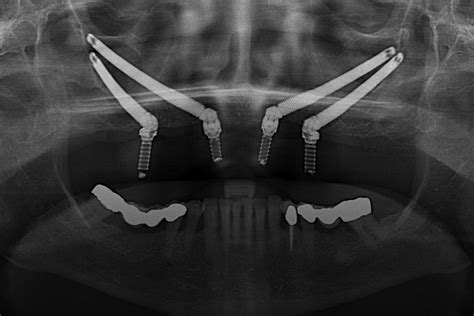

- Evaluación del paciente: La primera vez que un paciente acude a la clínica dental Torrefiel, el especialista revisa su dentadura, analiza su historial médico y se le hace pruebas de diagnóstico por imágenes con radiografía panorámica. La evaluación permite observar la calidad y cantidad de hueso del paciente, en base a esos resultados se determina si los implantes dentales sin tornillos son el procedimiento adecuado.

- Diseño del implante: Este paso es importante debido a que se crea una estructura metálica que se adapte a la fisionomía del paciente y soporte de forma adecuada la prótesis dental.

- Colocación de la estructura de titanio: Durante la cirugía el especialista hace un corte en la encía y abre un colgajo, después coloca la estructura de titanio sobre el hueso, ajustándose perfectamente a la forma del tejido óseo y fijándolo lateralmente con pequeños aditamentos que le dan mayor sujeción y estabilidad.